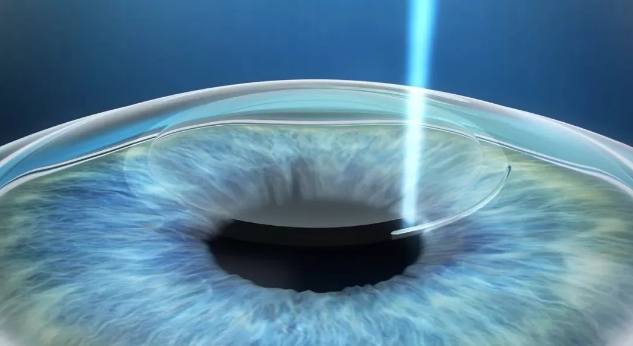

全飞秒激光SMILE

全飞秒激光SMILE是目前主流的微创角膜屈光手术,按照患者术前的检查数据,个性化地在角膜基质制作出一个基质透镜,再通过2-4mm左右微小的切口取出透镜。全程仅用到飞秒激光,无需转换机器,术中没有疼痛感;同时,小切口设计大程度地保护了角膜的生物力学稳定性。

全飞秒激光SMILE是低中度近视患者选择的主流手术方式。